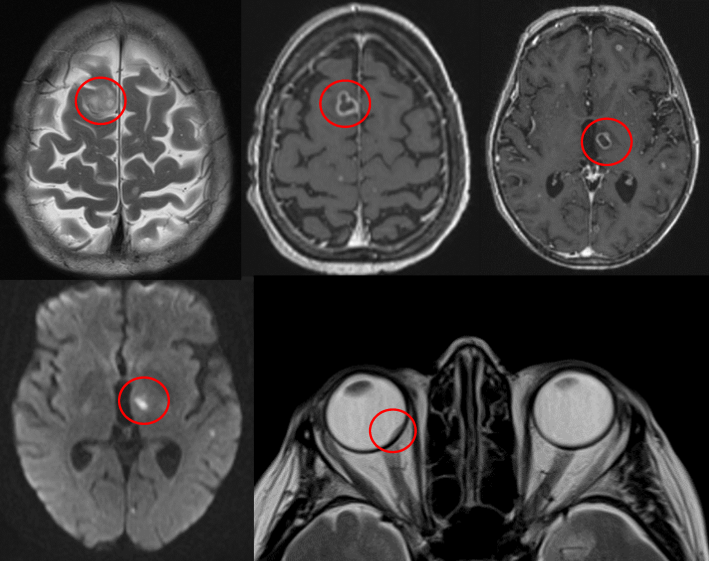

She was admitted from clinic and underwent an extensive array of investigations. Three positive blood cultures confirmed that she was suffering from Nocardia cyriacigeorgica and imaging revealed dissemination to multiple organs. Chest x-ray now showed segmental consolidation, MRI brain showed multiple punctate lesions consistent with disseminated CNS nocardiosis; high resolution CT chest now showed scattered lung nodules, MRI spine showed appearances suggestive of a right-sided psoas abscess secondary to discitis of L4/5, and normal transoesophageal echocardiography (Figure 3 [Fig. 3], Figure 4 [Fig. 4]).

Figure 3: MRI brain showing disseminated cerebral nocardiosis and choroidal abscess